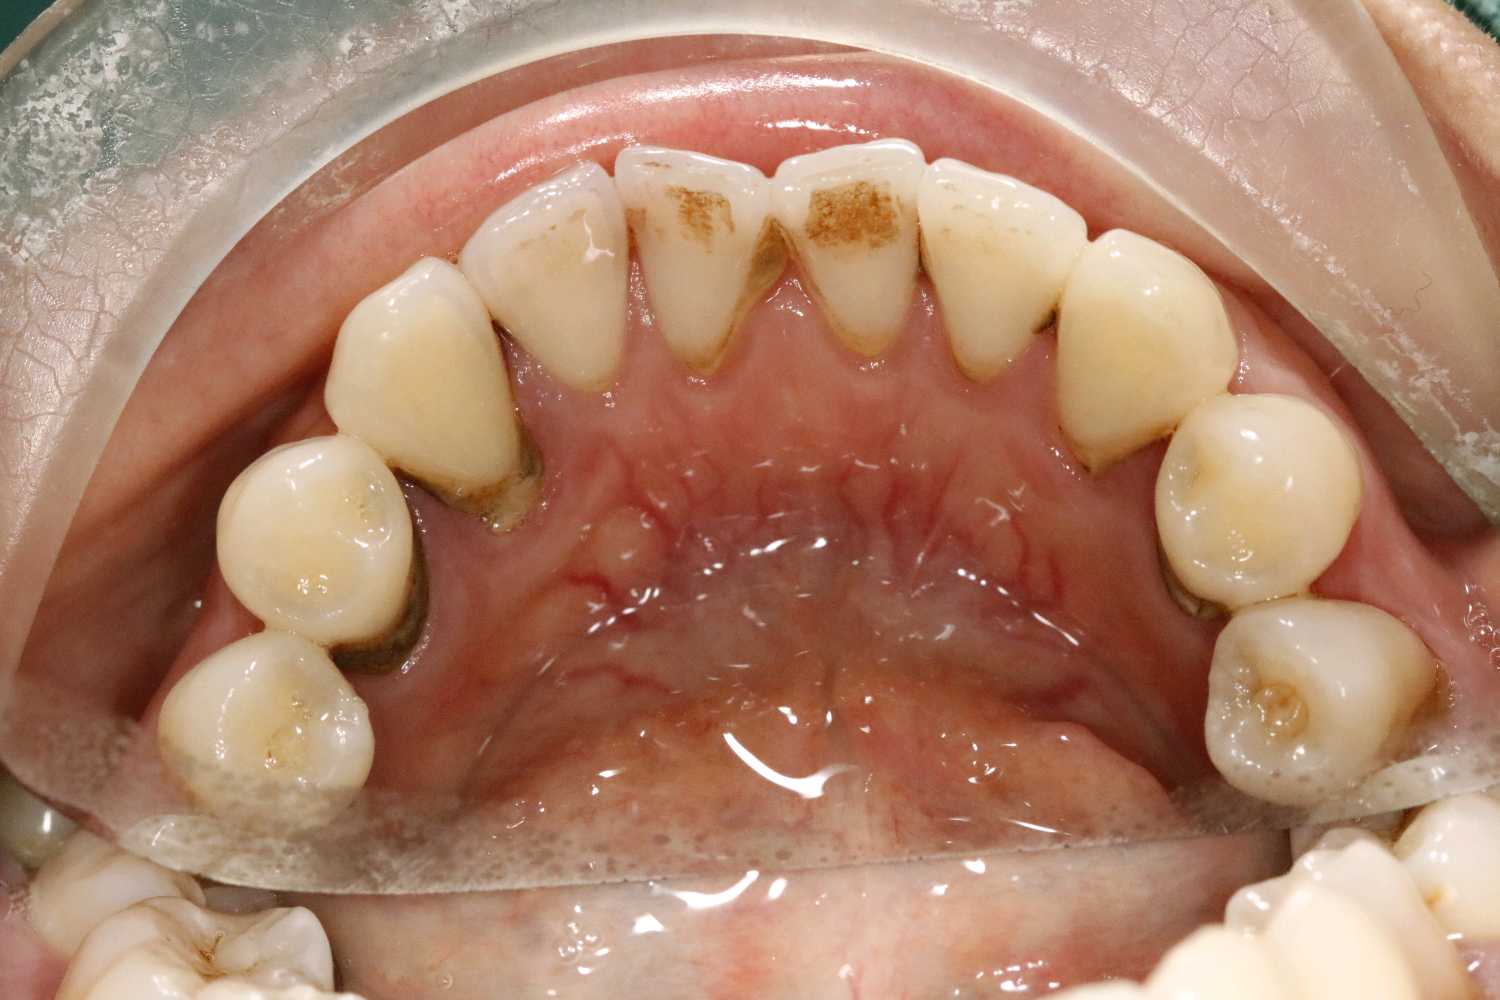

患者女三十岁,35畸形中央尖折断,根尖周炎症感染,导致牙根发育停止,根尖口呈喇叭口状。拔出后搔刮牙槽窝,颊侧骨壁吸收,植入骨粉骨膜。定期复查,将近半年见骨密度良好,骨量充足的条件下,行种植手术。植入3I 4/3*11.5mm的种植体。二期三期如期进行,与今日戴牙,患者满意。

二期术后